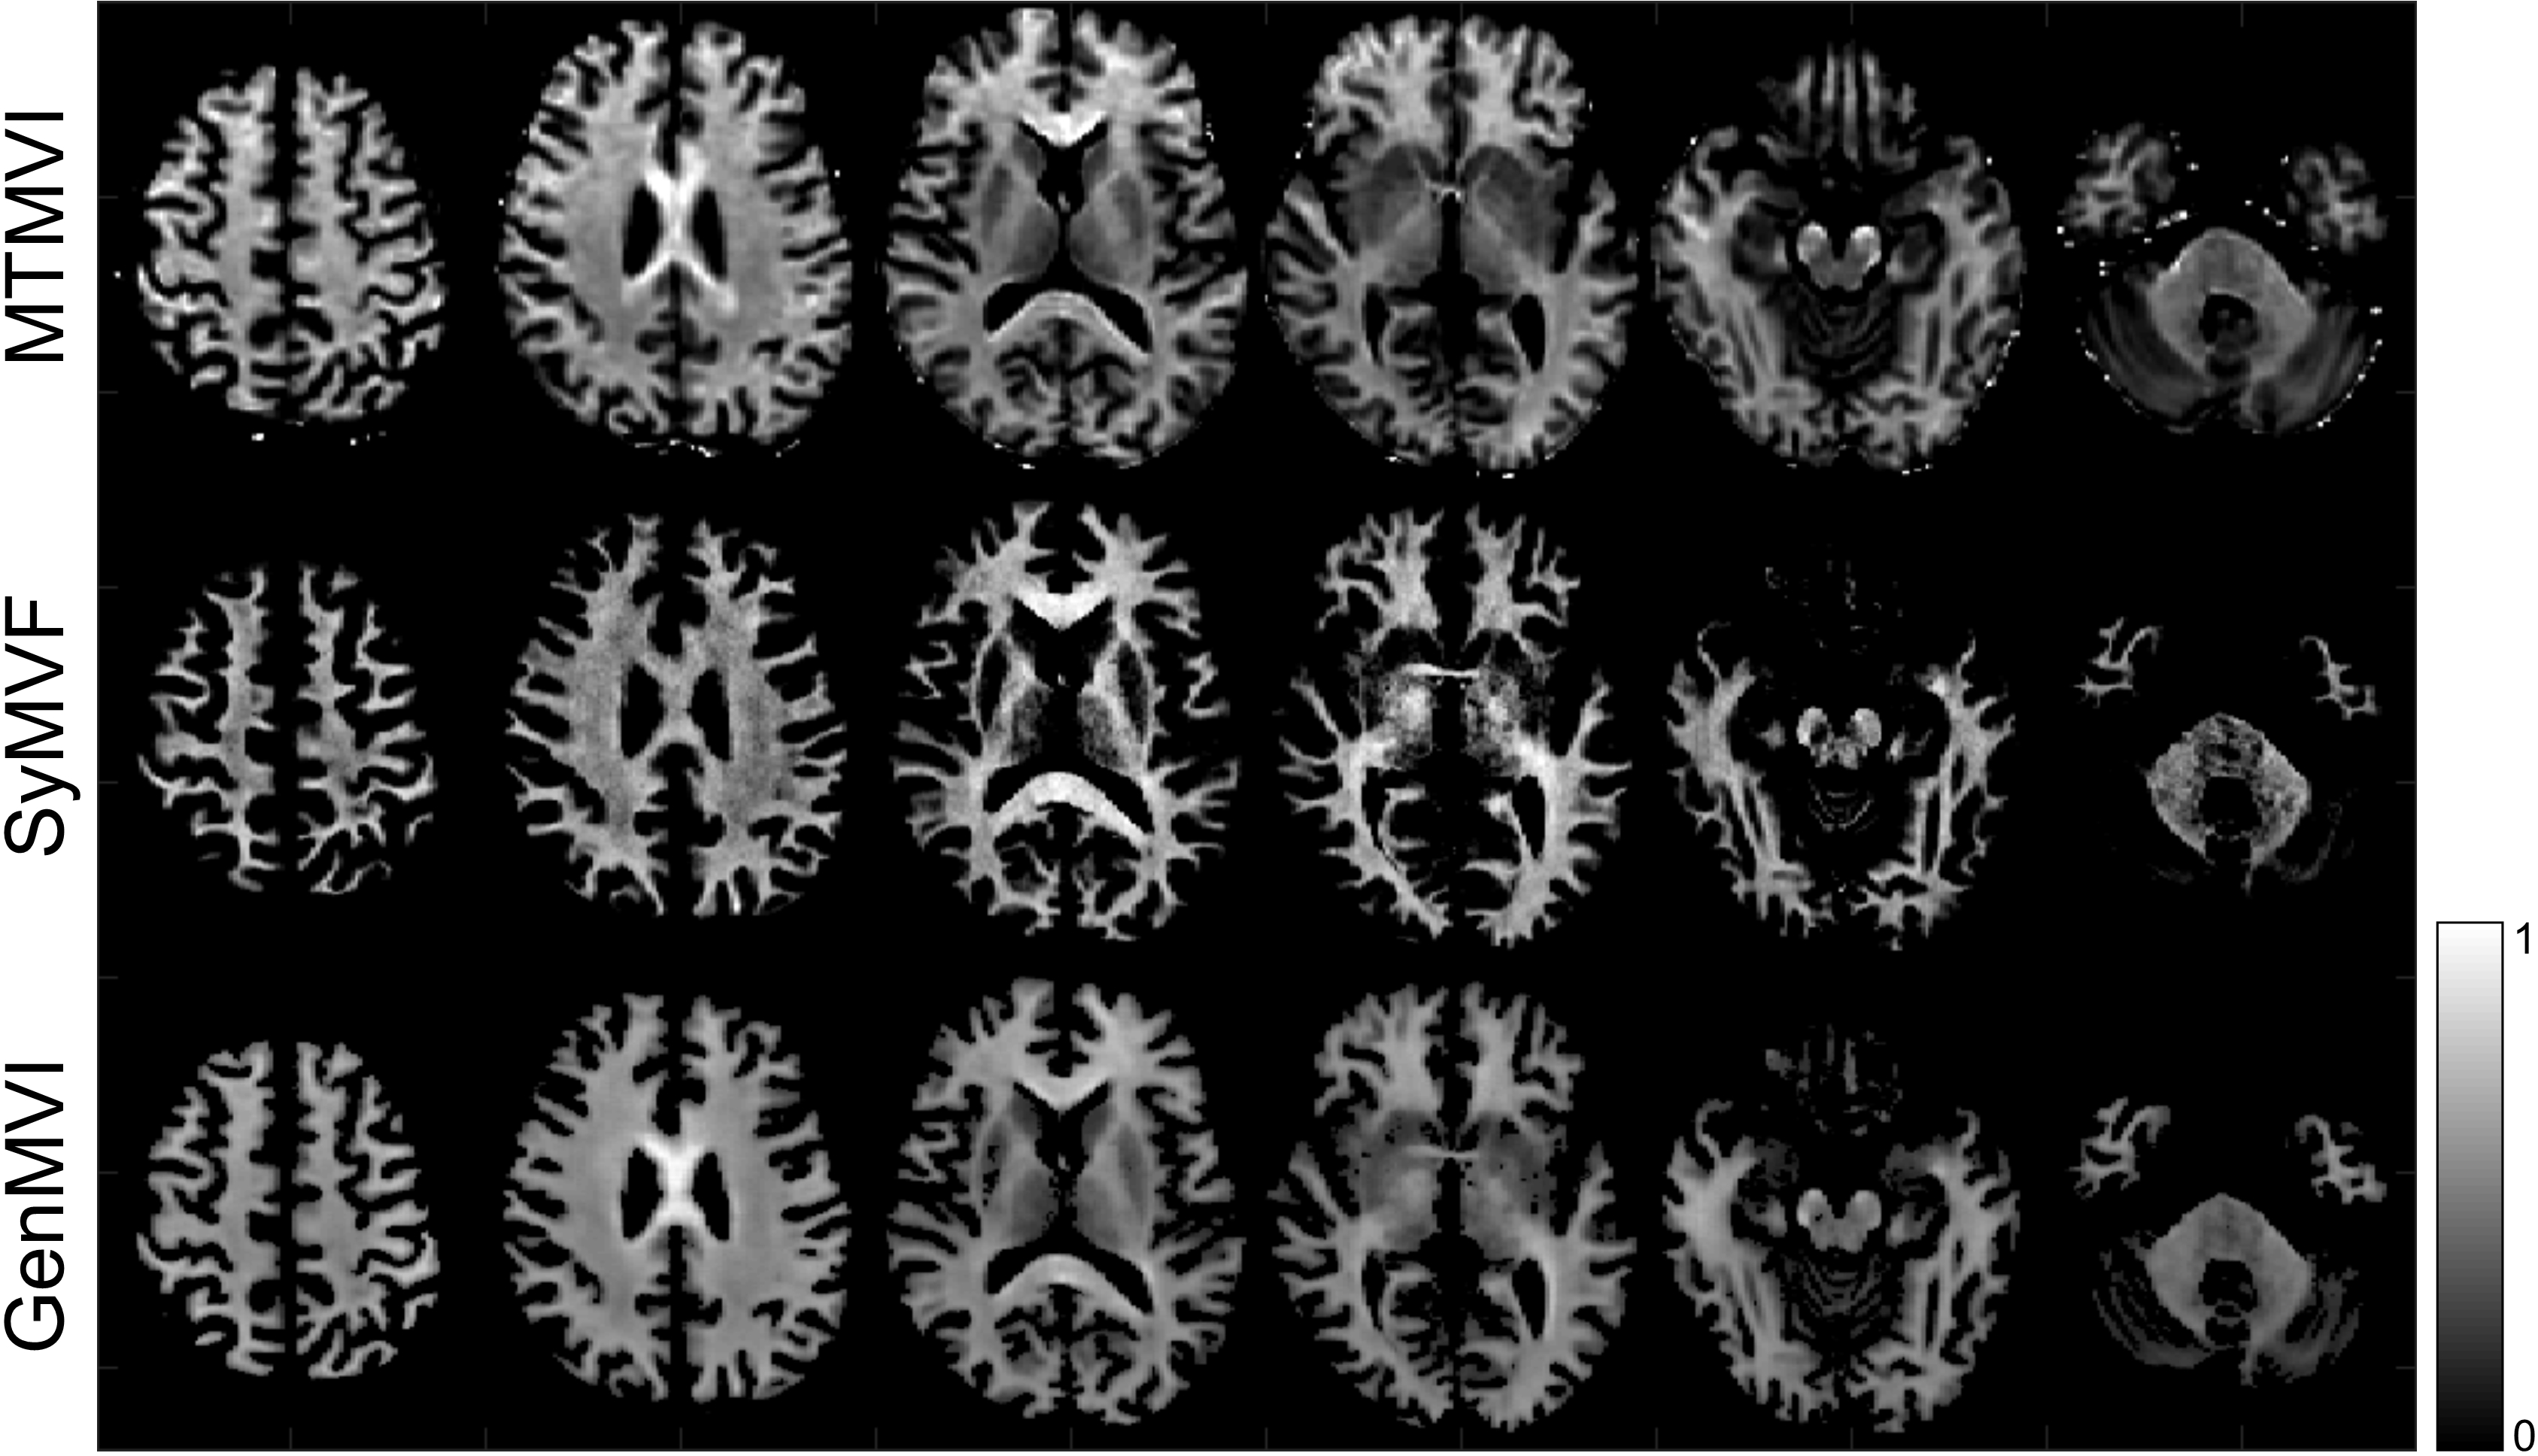

Examples of MTMVI, SyMVF, and GenMVI maps from the same volunteer are shown in Figure 2.

Figure 2: Typical MTMVI, SyMVF, and GenMVI maps obtained from the same volunteer. Visually, the contrast of the GenMVI map is more similar to MTMVI than that of the SyMVF map (See the corpus callosum area as a particular example).

Visually, the contrast of the GenMVI map was closer than the contrast of SyMVF to that of MTMVI (Figure 2). In particular, characteristics of the corpus callosum were better reproduced in the GenMVI map than in the SyMVF map. The corpus callosum was where the contrast was especially different between the SyMVF and MTMVI maps in a previous study [1]. The method proposed in this study appears to have improved this problem.

The pixel-based comparison performed for the corpus callosum indicated higher correlation for GenMVF over SyMVF, with a statistically significant difference between the two distributions (P<<.001) (Figure 5). This result is consistent with the visual evaluation of the region (Figure 2).